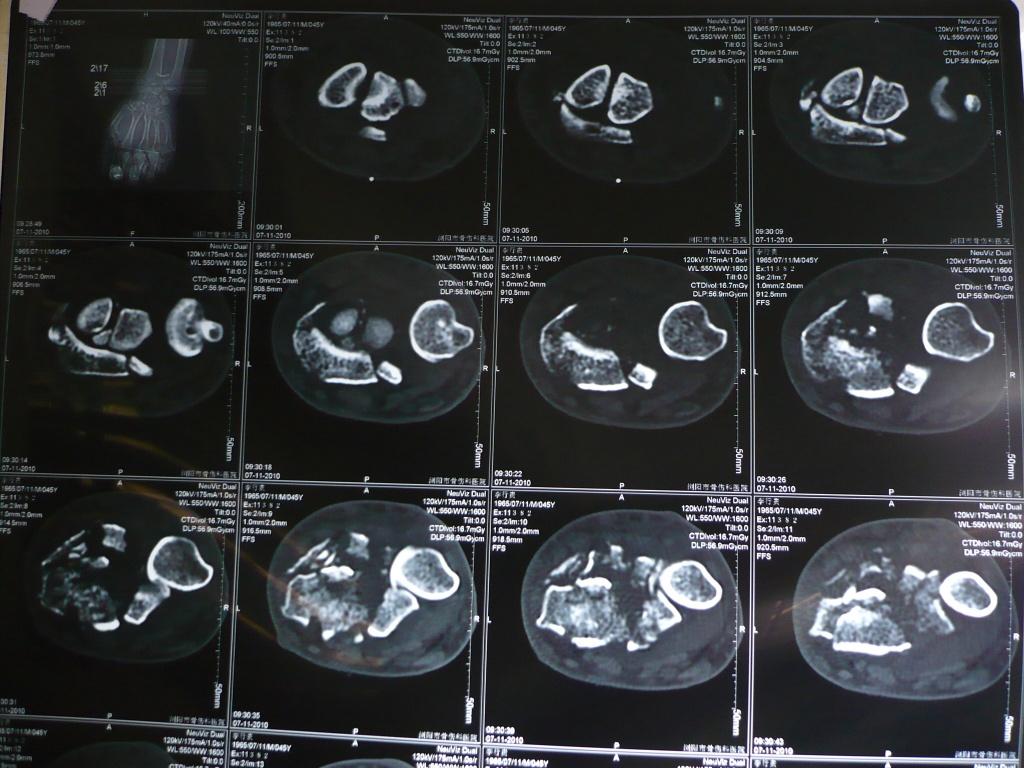

患者男性,45岁,外伤后6天,拟明天行开放复位内固定术。请战友指导手术方案及细节!

x片提示:右桡骨远端严重粉碎性骨折伴下尺桡关节脱位。建议:1.手法复位可能达不到想要的目的,关节面恢复不完整,创伤性关节炎不可避免。病员正是壮年,若是老年人,她对关节活动要求不高的话,也可以,(沟通清楚后)我们遇到很多老年患者,叫做手术,坚决不做,其要求不高。2.对于这个患者,建议手术治疗(手术目的:尽量恢复关节面的完整,恢复关节间隙),治疗方案有三:a掌背侧切开解剖复位,必要时植骨,细钢针固定,恢复关节面,缝合,外固定支架固定。 b,掌背侧切开解剖复位,必要时植骨,细钢针固定,恢复关节面,长的重建钢板自桡骨到第二掌骨固定。c术中看如果远端能曾受螺钉的话,也可以考虑“T”行钢板固定。